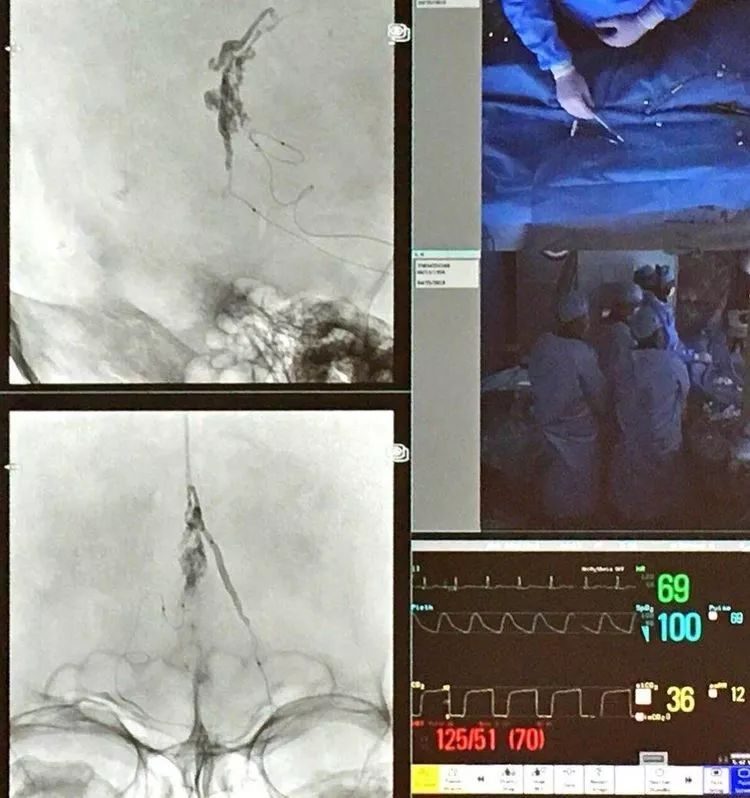

CASE 4 AN

-也是FD治疗,FRED Jr.血流重构

-采用最短的Fred jr,工作段在动脉瘤所在的细小分支,Jr近端无效工作段覆盖了较大分支

CASE 5 AN

-WEB是治疗分叉部动脉瘤的新武器

-WEB治疗复发的原因分析:一种解释是压缩造成的,wakhloo认为另外一个可能的原因是血栓的机化,机化的血栓可能牵拉WEB造成复发